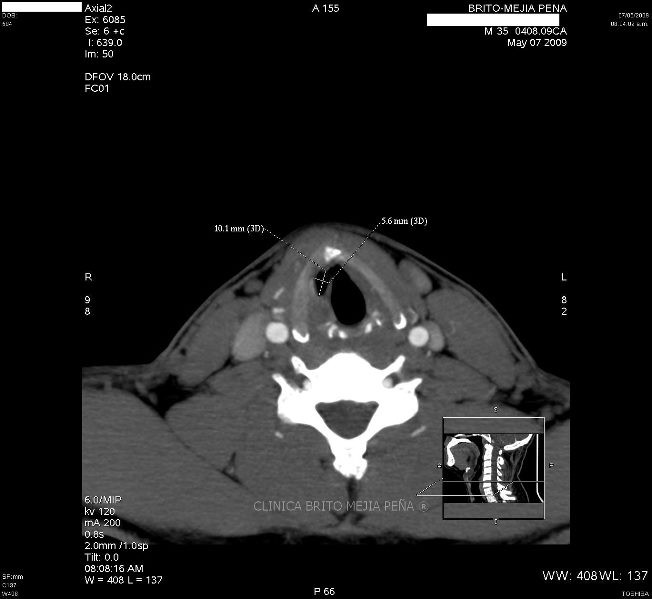

Detalle óseo